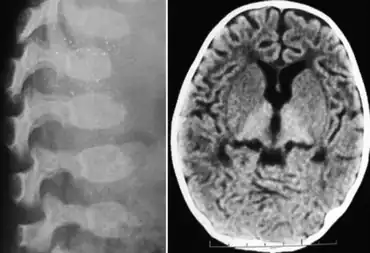

| GM1 gangliosidosis-X-ray indicates dysostosis multiplex at lumbar region and scan of brain indicates hyperdense thalamus | |

- Skeletal deformities: flexion contractures noted by 3 months; early subperiosteal bone formation (may be present at birth); diaphyseal widening later; demineralization; thoracolumbar vertebral hypoplasia and beaking at age 3–6 months; kyphoscoliosis. *Dysostosis multiplex (as in the mucopolysaccharidoses)